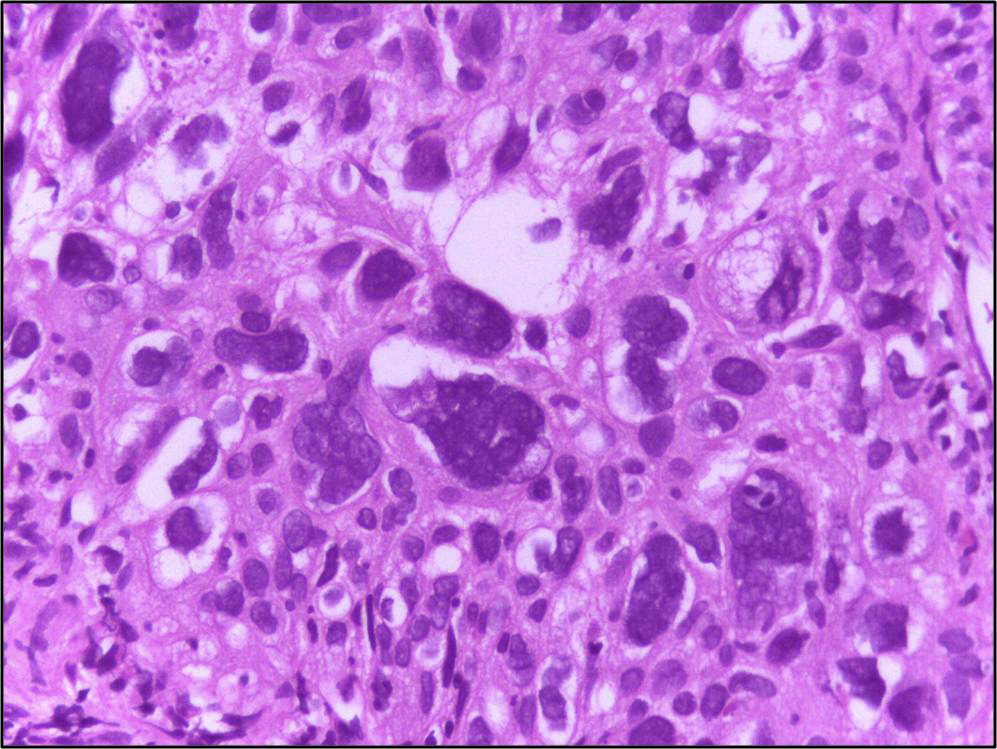

Chapter 1 Introduction to Pathophysiology; Cellular Responses to Stress, Injury, and Aging